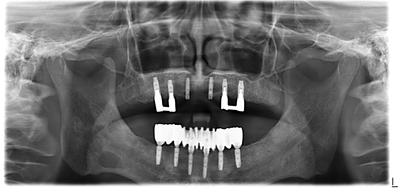

2022.11.14全顎的インプラント治療術後約10年

全顎的インプラント治療治療後約10年、何の問題もなくメインテナンス中。

下顎は固定式、上顎は義歯を使用。

上顎も固定式で対応可能だったが、前歯部の骨が薄く骨移植の必要性あったが、患者さんと相談の上、元々義歯を使用されていたこともあり、義歯で対応とした。

インプラントによる大幅な維持増大により、義歯は元と比較して相当小さくすることができ、違和感、咀嚼力は大幅に改善している。

食べられない物はないとの事、良かったです。